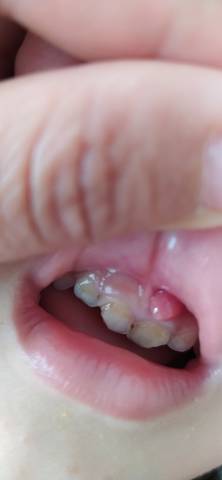

儿童牙龈瘤图片

3岁宝宝牙龈肿起来一个大包,这是怎么了?

五岁小孩下牙龈上长了一个红红的小肉瘤,摸上软软的不痛不痒是怎麼

小朋友上牙龈长出了个肉包包有图慎入有懂的帮忙看下

3岁4个月大的男孩宝宝,中间上门牙龈出现脓包,反复一直有

幼儿牙龈上长了个疙瘩,想问一下是怎么回事?需要怎么治疗,谢谢

这是怎么了,三周岁小女孩牙床上长个小包,不疼,吃什么药解决

宝宝牙龈上长了一个大包,摸着软的,是什么?如何治疗